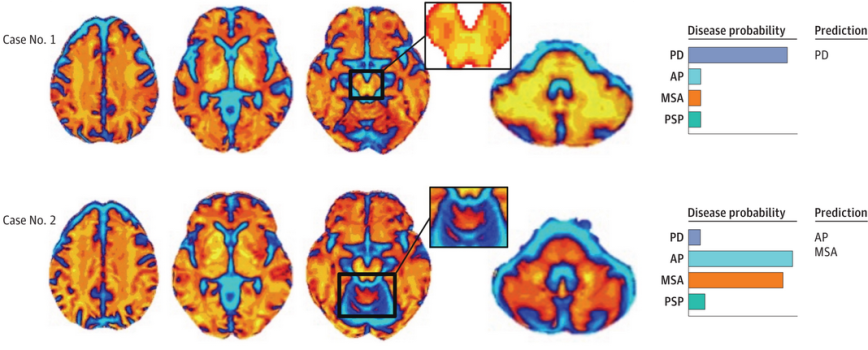

4. Automated Imaging Differentiation for Parkinsonism

A new prospective multicenter cohort study of Automated Imaging Differentiation for Parkinsonism suggests using this approach in the diagnostic workup for common parkinsonian syndromes, such as Parkinson’s & atypical parkinsonism (Click here to read more about this and click here to read a press summary on this research).